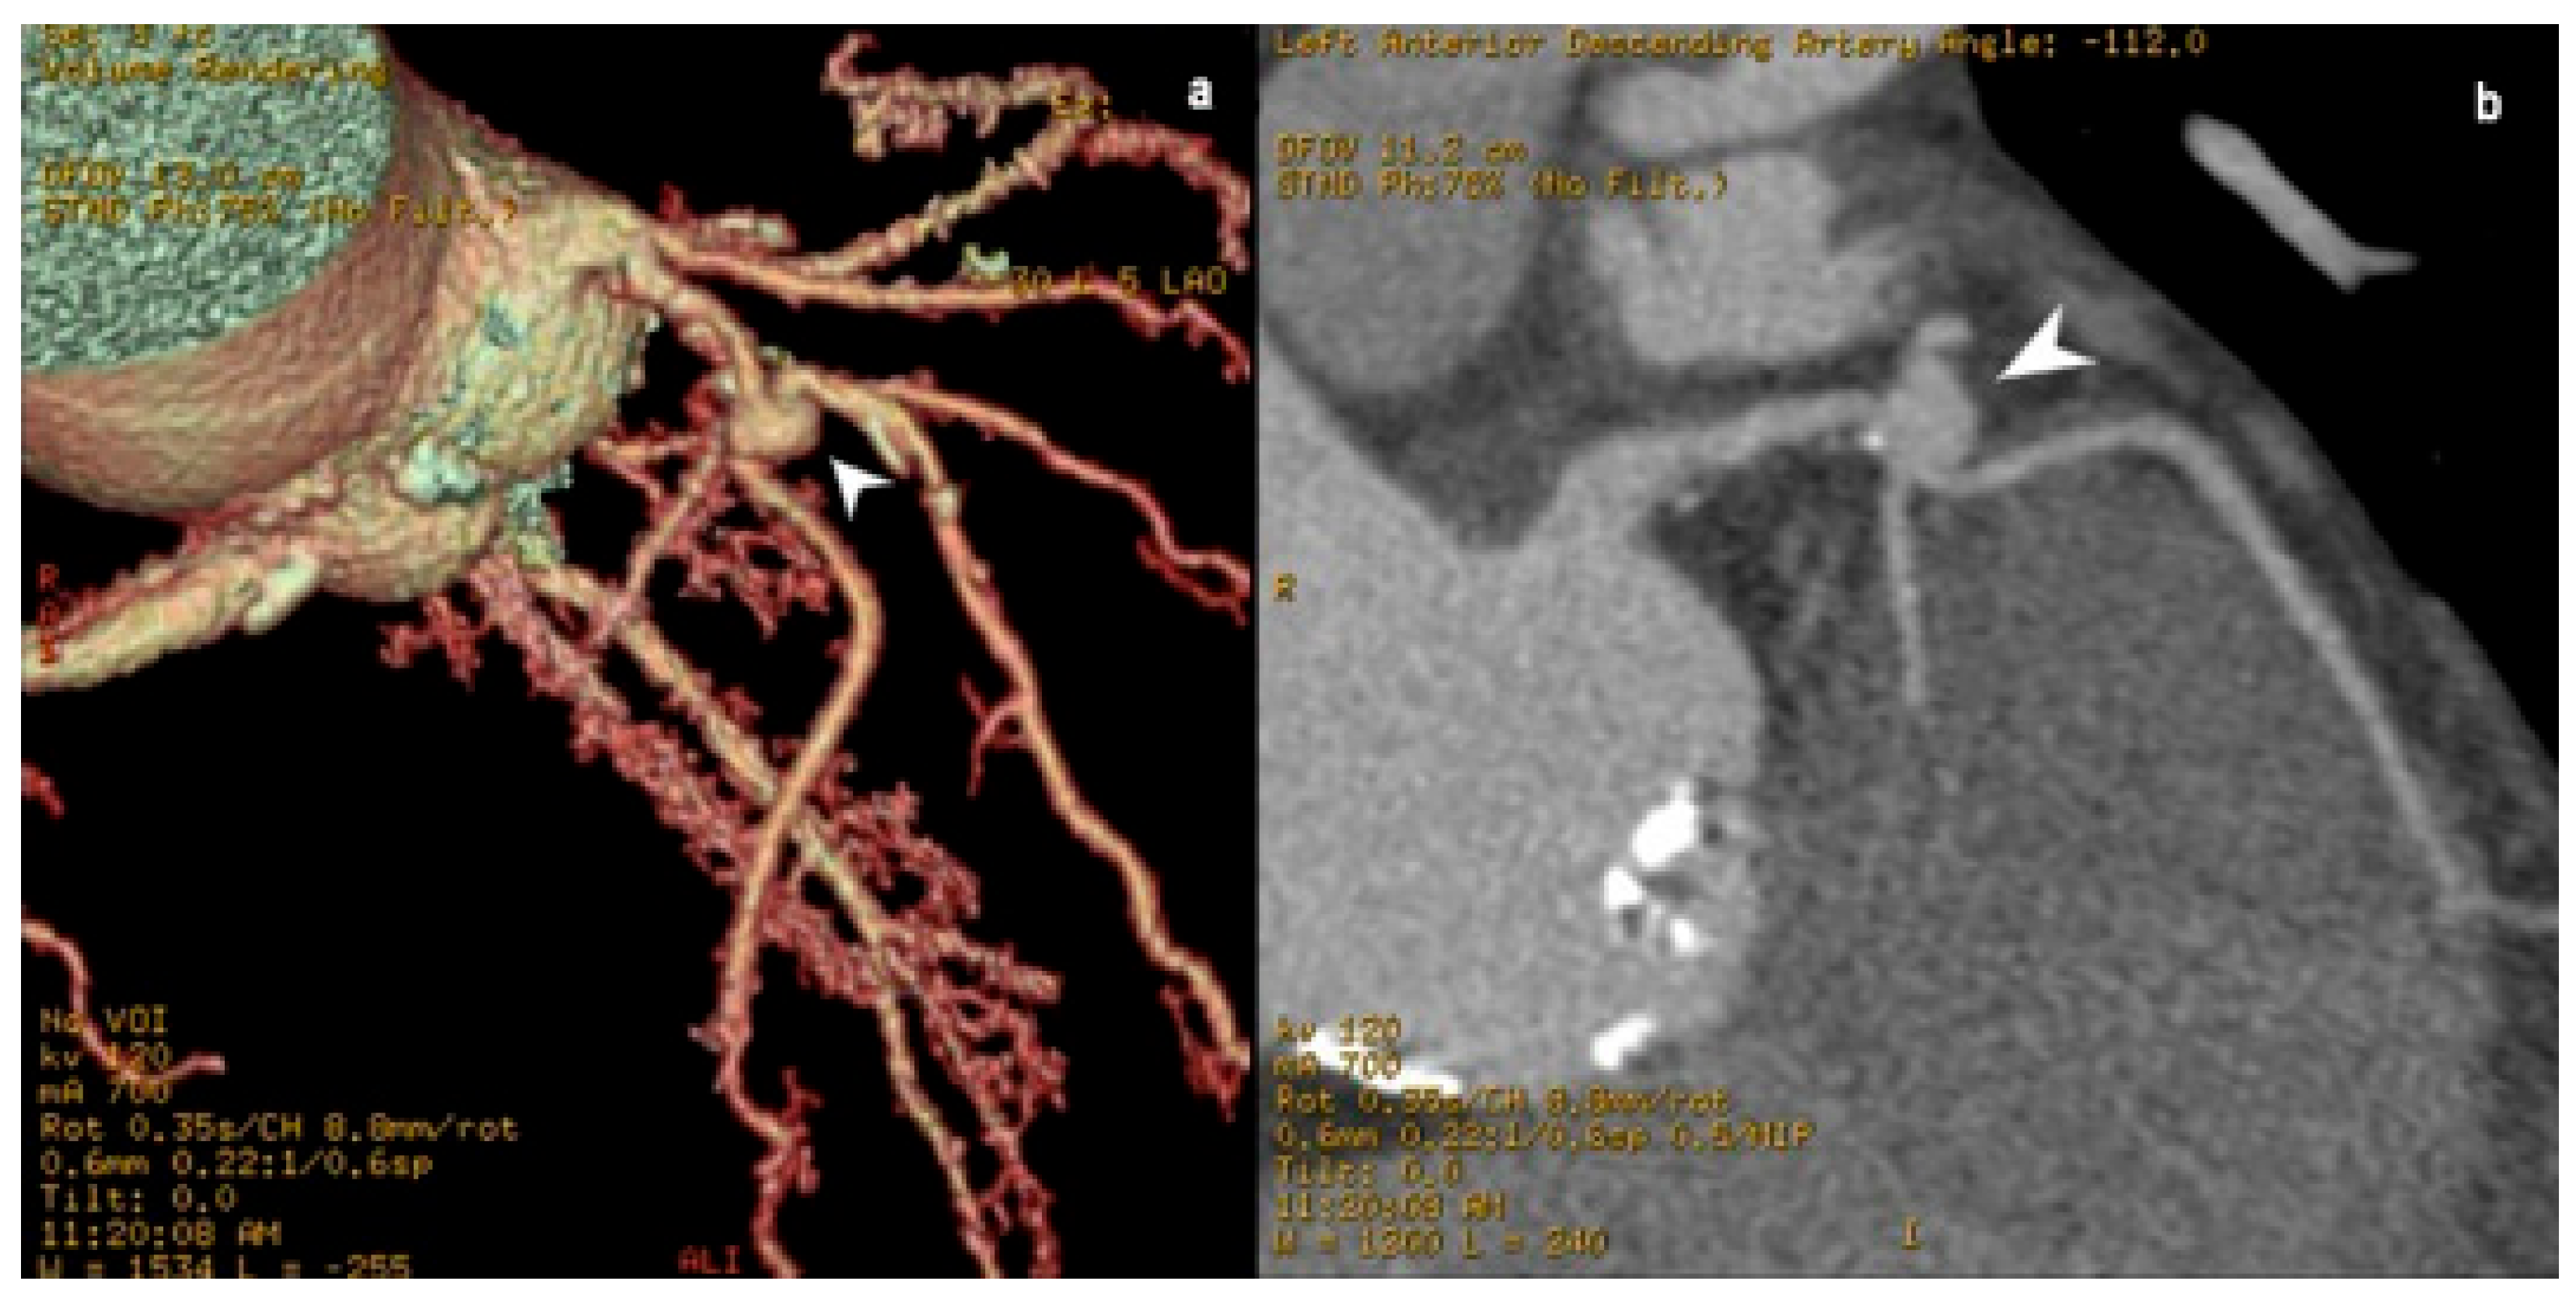

3.3. Coronary Arteriovenous Fistula